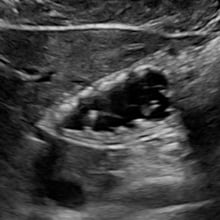

📚 Case Study: Echocardiography

What are the relevant sonographic findings?

Background:

80-year-old male presents with:

- Progressive dyspnea on exertion

- Normal vital signs

- No overt respiratory distress

👇 What type of pathology is in this clip?